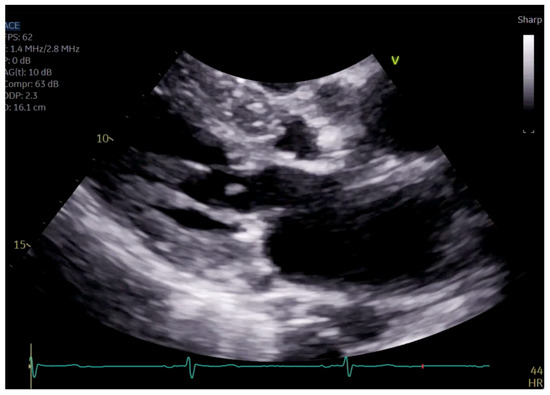

Transthoracic echocardiogram (TTE) showed severe asymmetric left ventricular hypertrophy, preserved left ventricular ejection fraction at 65–70%, systolic anterior motion (SAM) of the mitral valve (Figure 1 and Supplementary Video S1), left ventricular outflow tract (LVOT) obstruction with a peak velocity of 7.1 m/s at rest and an eccentric, posteriorly directed mitral regurgitant jet (Figure 2). Pharmacological myocardial perfusion SPECT with gated imaging was obtained one year prior to presentation and showed normal myocardial perfusion, left ventricular volume and systolic function. Cardiac magnetic resonance imaging showed left ventricular hypertrophy with a maximal thickness of 1.7 cm at the mid-ventricular septum and late gadolinium enhancement in the lateral and inferior half of the left ventricle, the basal inferolateral wall, the apical lateral walls and the apical anterior wall (Figure 3a,b). These findings were consistent with a diagnosis of HCM with outflow tract obstruction; thus, the patient was started on beta blockers.

Figure 1.

Parasternal long axis view on TTE showing left ventricular hypertrophy and SAM.